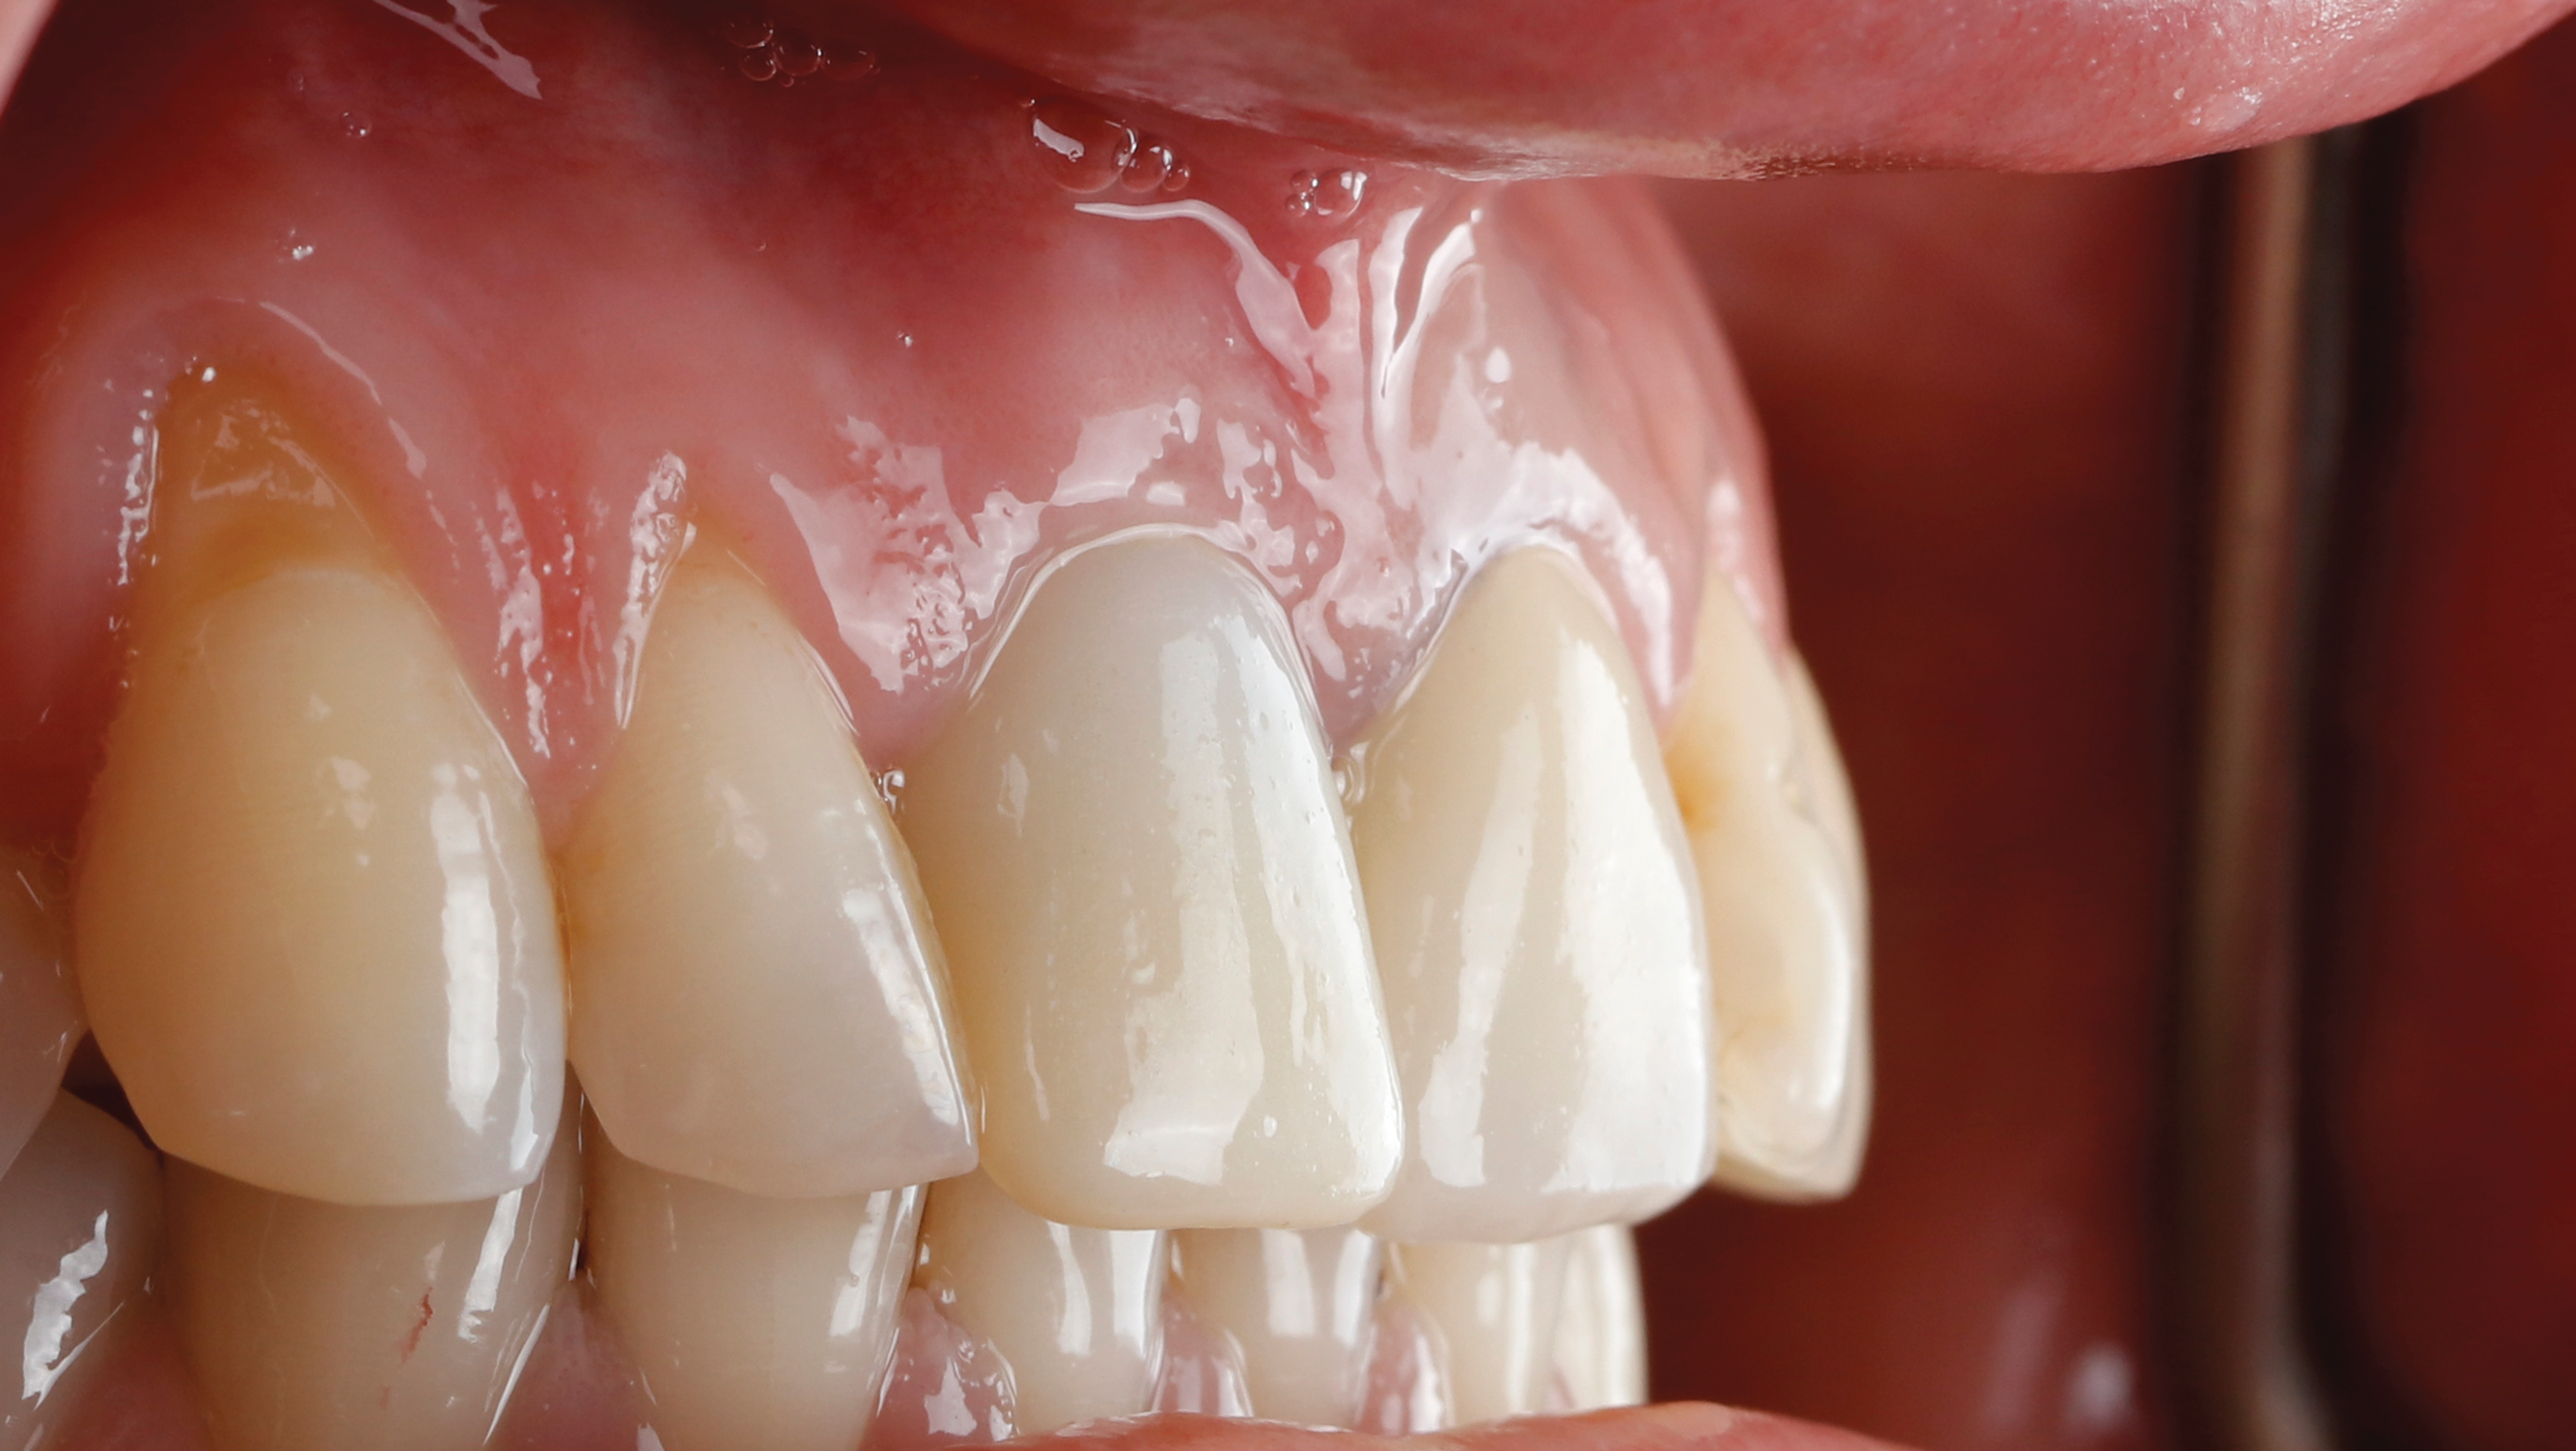

Fig 19. At 3 months postoperative, note maintained soft- and hard-tissue volume.

Figure 19

Fig 20. At 6 months postoperative, the right central incisor site demonstrated significant hard- and soft-tissue volume maintenance. The left central incisor tooth was prepared for a new restoration.

Figure 20

Fig 21. One-year postoperative, final crown restorations. Note soft- and hard-tissue volume maintenance in the right central incisor (socket-shield site).

Figure 21

Follow-up images for the case presented, demonstrating a successful restoration, are shown in Figure 18 through Figure 22.